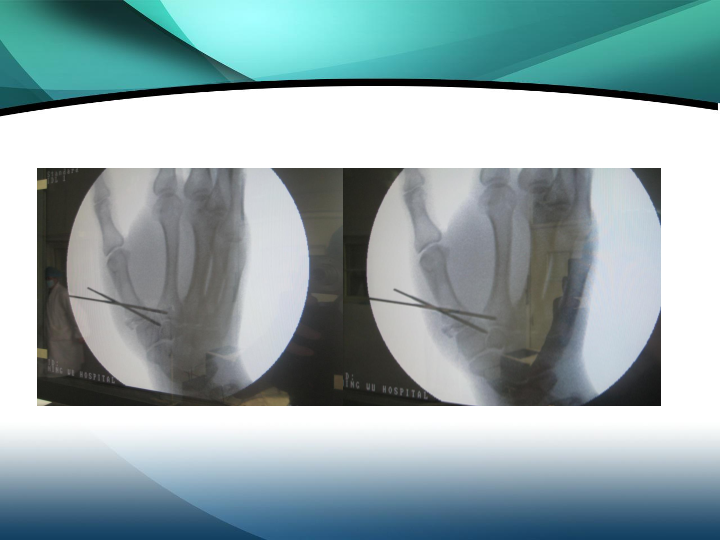

掌骨骨折